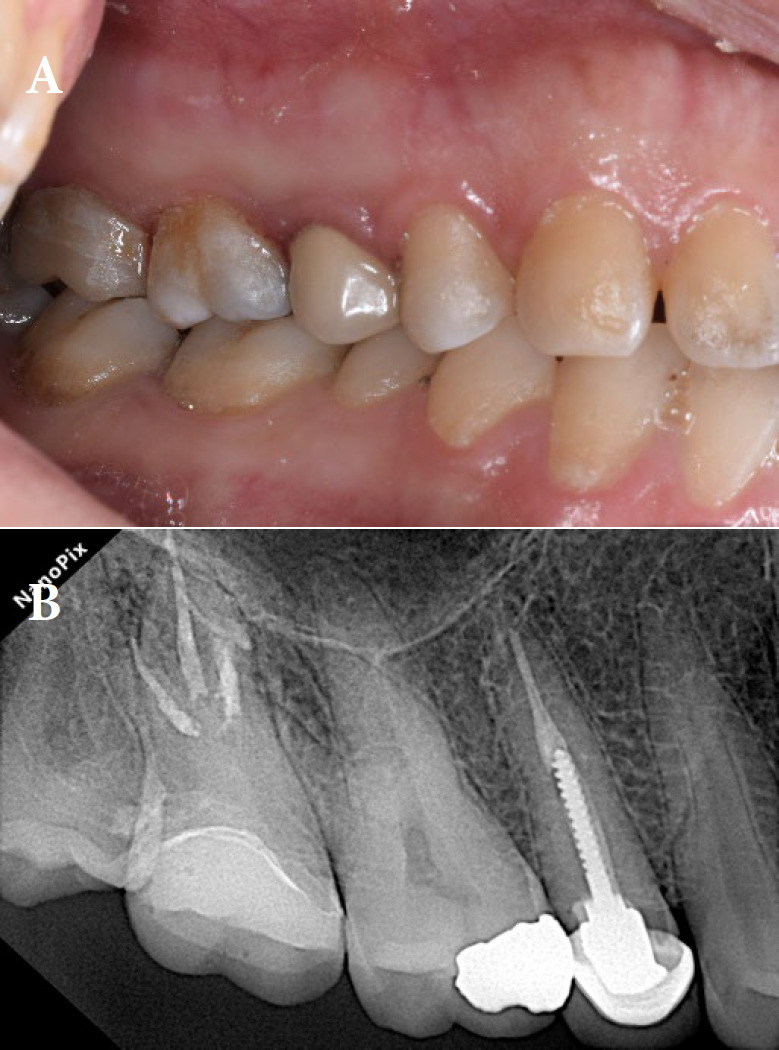

Taurodontism is a dental anomaly characterized by an enlarged pulp chamber and apically displaced pulpal floor. This disorder poses significant challenges in endodontic treatment, especially when perforations occur. The present case study details the endodontic retreatment of a hypertaurodont maxillary second molar in a 36-year-old female patient with a mesial canal perforation. The procedure employed a dental operating microscope for enhanced visualization and precision. Canals were prepared using a crown-down technique, with the perforation site managed using MTA and bioceramic material applied via the second mesiobuccal canal. The remaining canals were obturated using gutta-percha and bioceramic sealer. At the 1-year follow-up, the tooth was functional and asymptomatic, with radiographic evidence of a normal periodontal ligament space. This case demonstrates the efficacy of contemporary endodontic techniques, including bioceramic materials and advanced magnification, in managing the unique challenges posed by taurodontism.